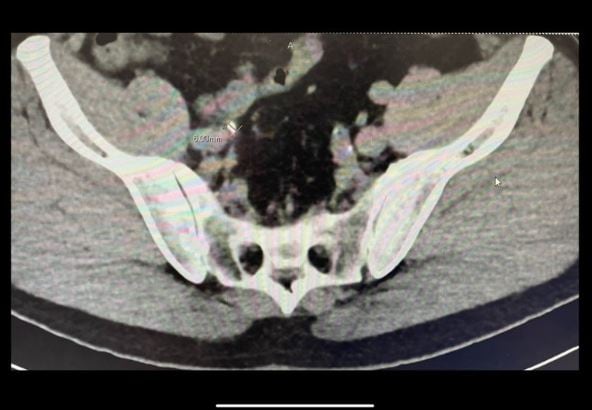

富澤さんは写真をアップし「もう何回目になるのだろう?今回は約6ミリの石を確認。一度痛みは来たのでもう来ないといいのですが。」と、不安な思いをファンに伝えています。